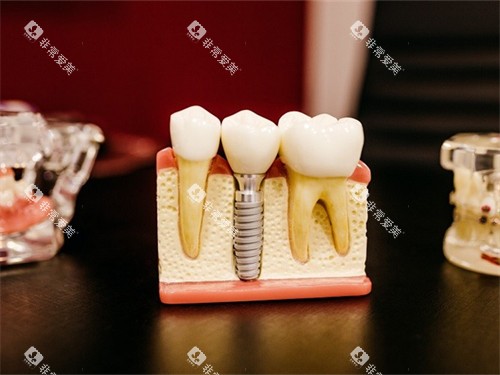

医生团队擅长3D小创口舒适种植技术,单颗种植手术时间缩短,术后改善周期降低。

诊所引进德国卡瓦种植机、丹麦3shape口腔智能化扫描仪等设备,实现种植体植入误差控制在极小范围。

诊所擅长骨性龅牙矫正与ALL-on-4半口全口种植技术,田场磊医生团队通过微笑美学设计,使种植牙与天然牙形态协调度提升。